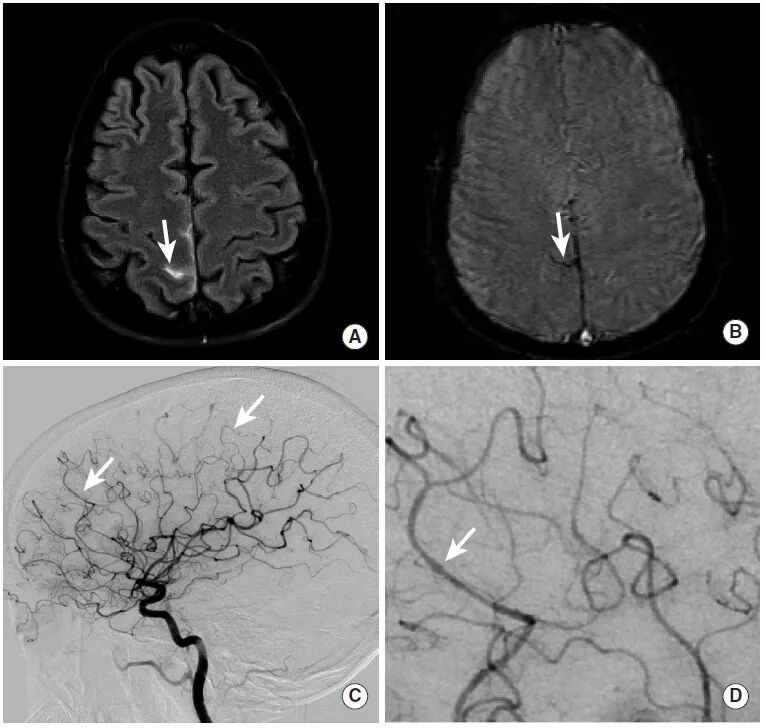

图17

本例为继发于右侧大脑中动脉真菌性动脉瘤破裂的蛛网膜下腔出血。

图A~C:MRI的FLAIR序列及GRE序列均证实蛛网膜下腔出血(图A、B),增强扫描则显示左中央前沟沿着血管走行的圆形强化区域,即真菌性动脉瘤。

图D~F:DSA显示出位于左侧中央前动脉的分叶状真菌性动脉瘤。这种真菌性动脉瘤在横向放大视图中显示最佳。